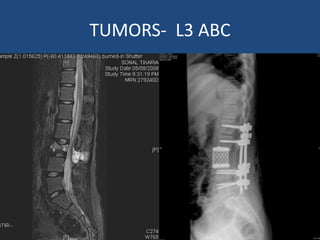

L3 Primary Bone Tumor

TUMORS- L3 ABC